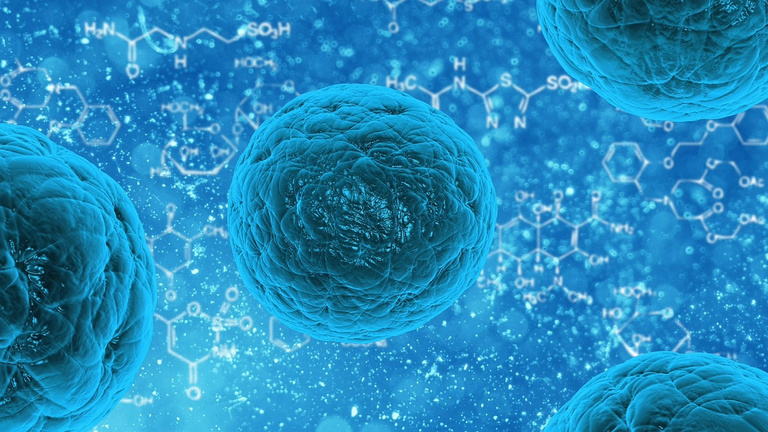

How Does Cell Therapy Works?

As we age our cells gradually lose their ability to function precisely as they were intended. Cell therapy stimulates secretions that activate the aging or decreased cells to get back on track and function properly. In other words, cellular therapy works by prevention, the therapy stimulated the aging organ to regenerate.

This restoration usually takes about 2 to 3 months to see progress. To have cell therapy in Switzerland may easily cost not less than Php 2.6M+ excluding accommodations, etcetera.

Now, with high technology, Celergen has made it possible for you to get a wide range of benefits from cellular therapy without having to visit Switzerland.

Celergen philosophy encapsulates the transformative power of cell therapy which aims at direct stimulation of regeneration of patients own mal or non-functioning cells.

Unlike other cell therapies, which involve injections, Celergen comes in an oral soft gel. Clinically proven and potently encapsulated with the essential elements of Marine DNA Cellular Extracts, Celergen stimulates our own natural healing powers to trigger the repair and rejuvenation of cells by providing biologically active micronutrients and essential nutrition at the cellular level.

The potent active key ingredient is a proprietary Cellular Marine Complex that is extracted from the DNA of deep-sea marine life, which through nearly 30 years of research has been associated with powerful anti-aging properties.

Other ingredients include Peptide E Collagen, which reinforces skin elasticity, Hydro MN Peptide, which plays a critical role in the rejuvenation of cartilage, and Natural Lutein, Coenzyme Q10 and Selenium. This synergistic blend restores the firm, youthful complexion you desire.